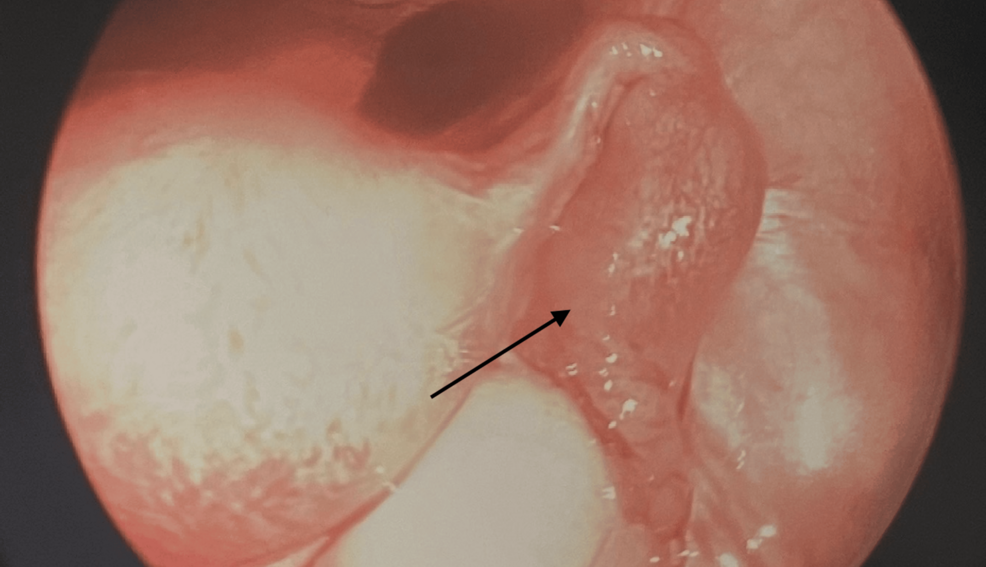

Las embarazadas bilaterales en las trompas de Falopio son la forma más rara de embarazo extrauterino, con una incidencia mayor en mujeres que están pasando por la ovulación.